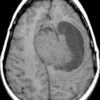

U màng não - Ảnh 3

U màng não

» Thông tin: Nam giới – 70 tuổi.

» Lâm sàng: Đau đầu.